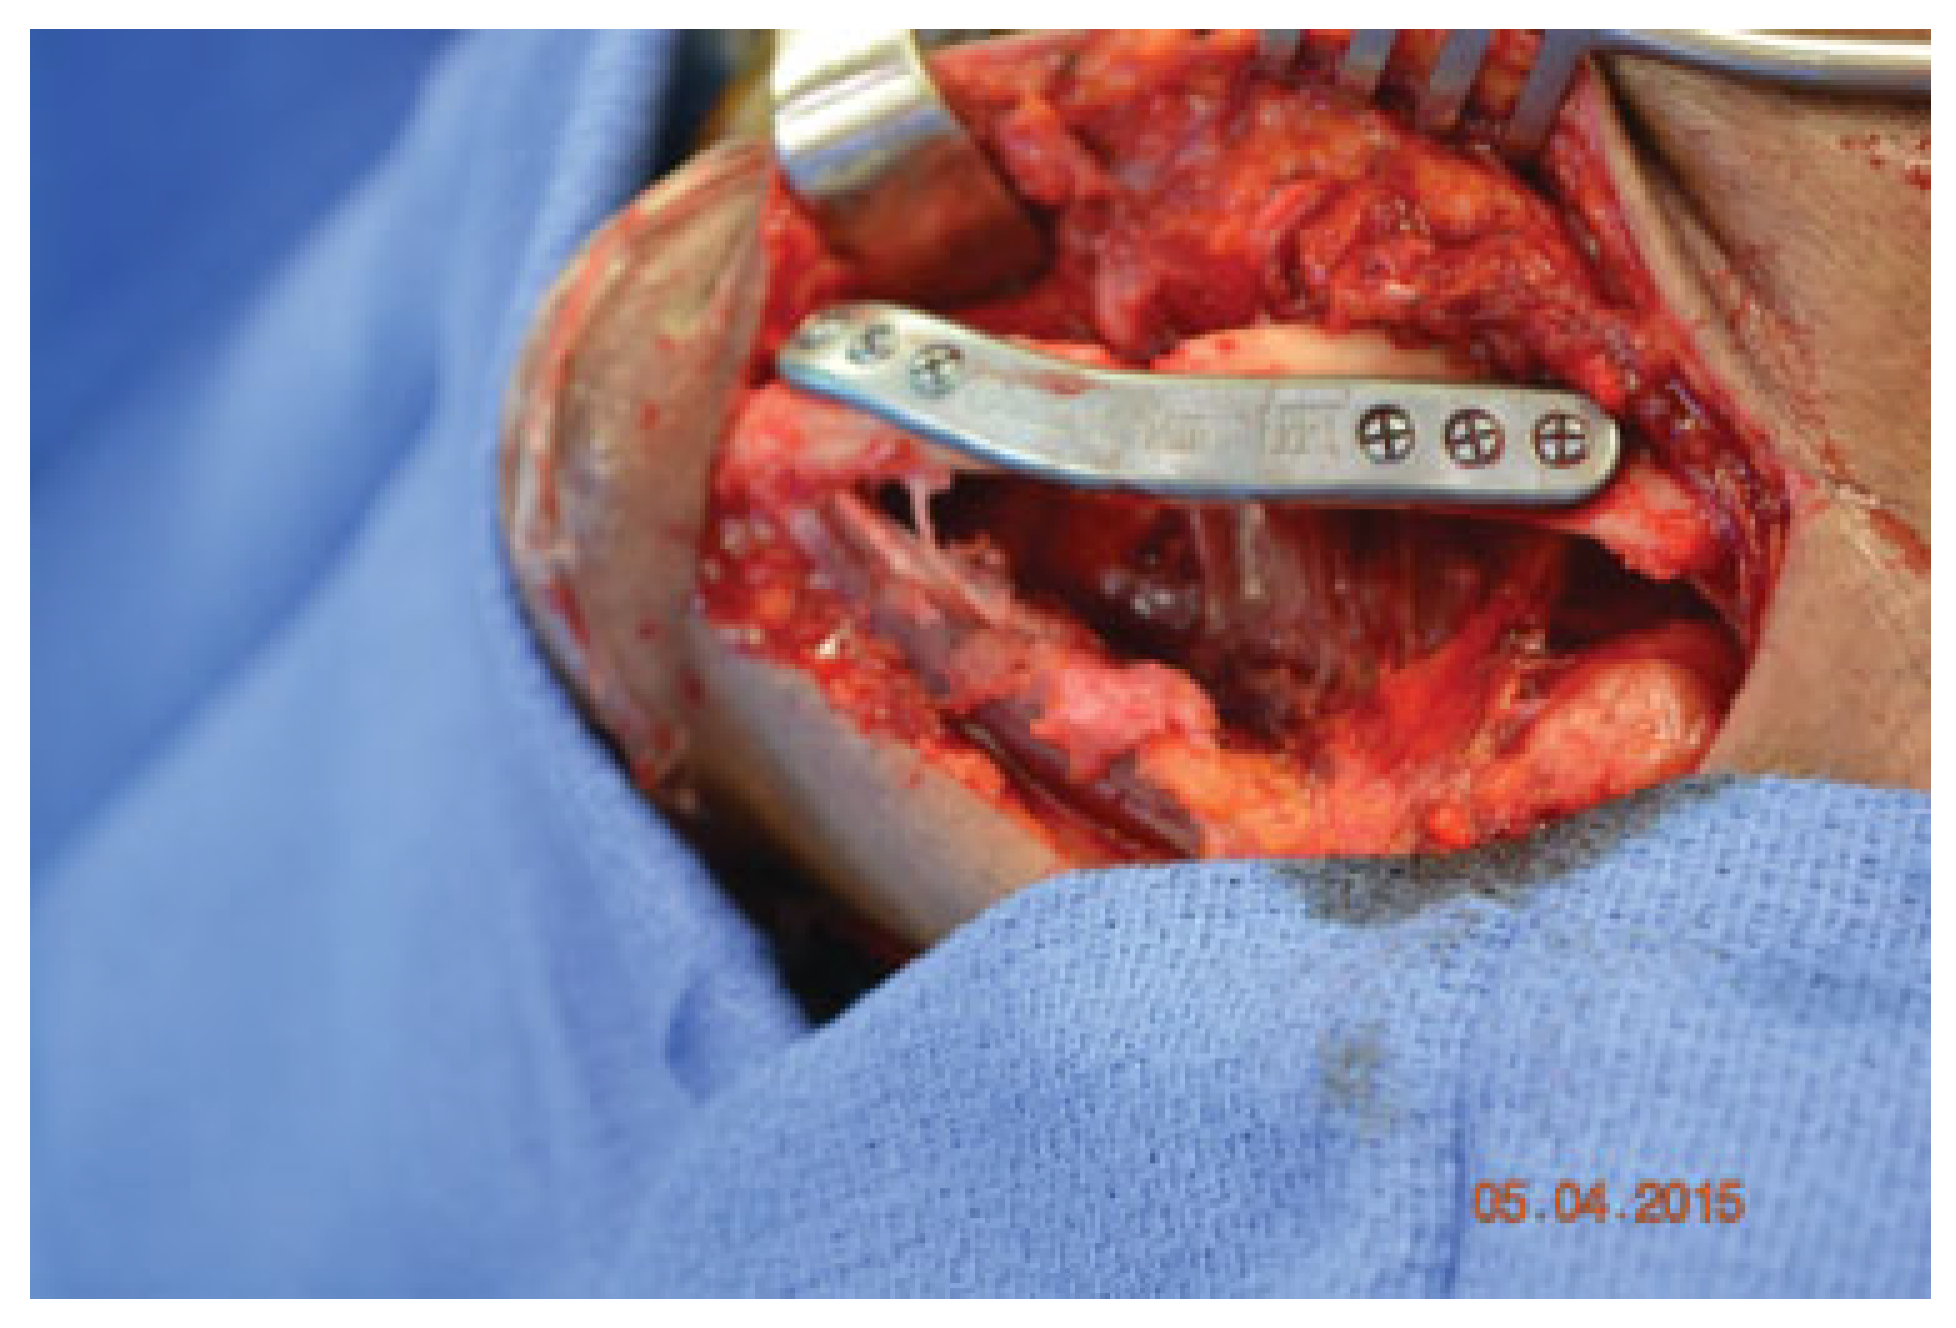

An extended submandibular approach was used and the mandible was exposed from angle to angle. The prebent plate was utilized to aid in the alignment of the segments and multiple bicortical locking screws were used (Figure 5). Multiple small fragments of bone were removed, the fracture sites were then debrided, and allograft (DBX Demineralized Bone Matrix–Musculoskeletal Transplant Foundation, Edison, NJ) was placed into the fracture sites. Layered closure was then performed (Figure 6). A postoperative panoramic radiograph showed good reduction of the fractures, intact hardware, and good plate adaptation (Figure 7). The patient was discharged on postoperative day 1. She was seen at 2 weeks and 6 months postoperatively and her injury healed well without complications.

Figure 5. Intraoperative photo of prebent hardware fixation.